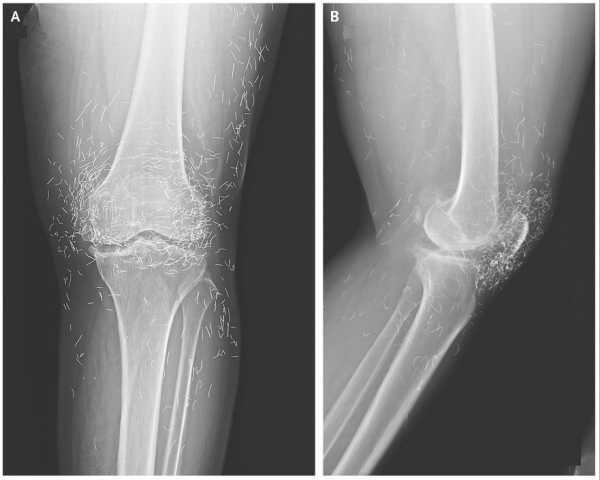

Woman’s severe knee pain reveals ‘golden threads’ in her joints